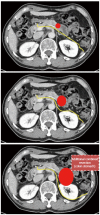

Minimally invasive distal pancreatectomy with splenectomy has been regarded as a safe and effective treatment for benign and borderline malignant pancreatic lesions. However, its application for left-sided pancreatic cancer is still being debated. The clinical evidence for radical antegrade modular pancreatosplenectomy (RAMPS)-based minimally invasive approaches for left-sided pancreatic cancer was reviewed. Potential indications and surgical concepts for minimally invasive RAMPS were suggested. Despite the limited clinical evidence for minimally invasive distal pancreatectomy in left-sided pancreatic cancer, the currently available clinical evidence supports the use of laparoscopic distal pancreatectomy under oncologic principles in well-selected left sided pancreatic cancers. A pancreas-confined tumor with an intact fascia layer between the pancreas and left adrenal gland/kidney positioned more than 1 or 2 cm away from the celiac axis is thought to constitute a good condition for the use of margin-negative minimally invasive RAMPS. The use of minimally invasive (laparoscopic or robotic) anterior RAMPS is feasible and safe for margin-negative resection in well-selected left-sided pancreatic cancer. The oncologic feasibility of the procedure remains to be determined; however, the currently available interim results indicate that even oncologic outcomes will not be inferior to those of open radical distal pancreatosplenectomy.